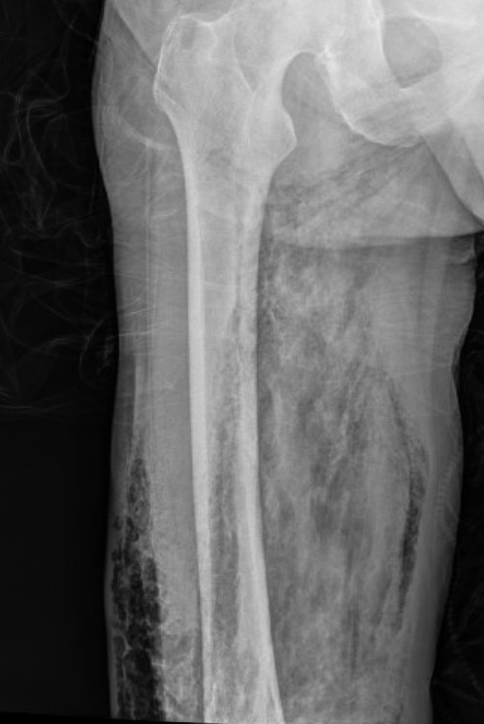

Below is a case of extensive right lower extremity necrotizing fascitis with diffuse subcutaneous emphysema.

Right femur: